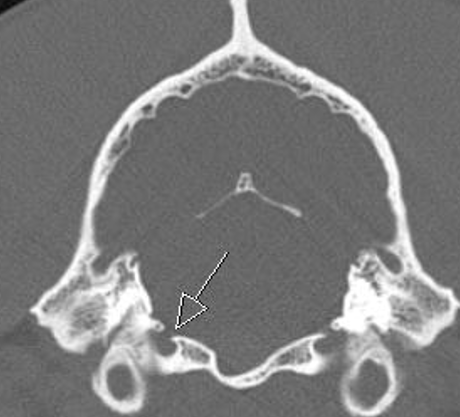

hypoglossal canal